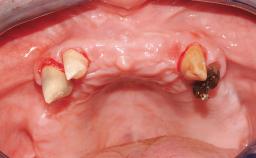

Immediate Loading of Eight Implants in the Maxilla and Six Implants in the Mandible and Final Restoration with Three-Unit and Four-Unit FDPs

Extensive scientific evidence has confirmed that immediately loaded implants with fixed full-arch provisional restorations can osseointegrate with success rates similar to conventionally or delayed loaded implants. A number of immediate-provisionalization techniques for edentulous jaws have been described. Some protocols differ when it comes to prefabricated provisional templates versus complete denture conversion; intrasurgical impressions versus direct relining; and cemented versus screw-retained provisional restorations. In this context, complete-denture conversion has been proposed for either intrasurgical impressions or direct relining. Another possibility is the utilization of a prefabricated provisional to be adapted either in the mouth (by direct relining) or in the laboratory (on a working model obtained from an intrasurgical impression).

Case Type Edentulous Maxilla

Soft Tissue Anatomy Intact Defective

Bone Volume Horizontally and vertically sufficient Horizontally deficient Deficient vertically or deficient vertically AND horizontally